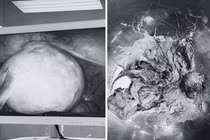

u-quai.jpg

Khối u nặng 1,3 kg được bóc tách thành công. Ảnh: BVCC.

Sau 5 giờ phẫu thuật, các bác sĩ đã bóc tách thành công khối u nặng 1,3 kg. Sau mổ, bệnh nhi hồi phục tốt và tiếp tục được hóa trị theo phác đồ điều trị.